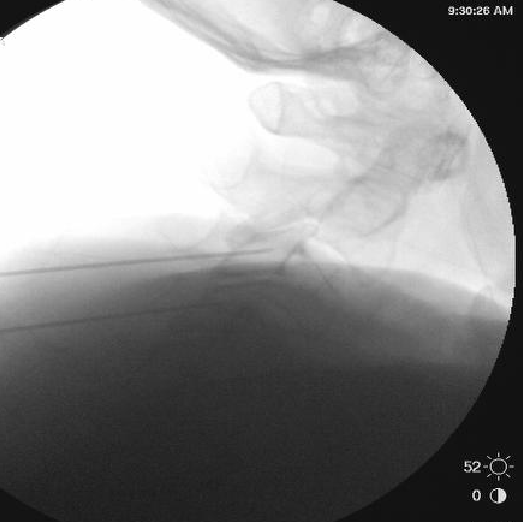

Only thing I do differently is aim for a touch more posterior placement of the needle. I try to make sure the very tip of the needle is at but not beyond the x in the image below. I also take a final lateral right before RFA. I think it helps reduce the frequency of neuritis to be a bit more posterior.

I appreciate the input, but I'm using a 10mm active tip and I'm burning quite a bit of MBN in that pic right there. Going more posterior theoretically means I'm getting less of it.

I think there is a very substantial cutaneous aspect to these nerves.

Based on some discussion on here a few years back, I tried burning 1/2 way along the pillar rather than anterior edge, but felt like I saw an immediate increase in neuritis. I suspect there are at least 2 different causes. Some neuritis comes from burning nerves with a sensory input to the skin, unavoidable, but some comes from being a little off target and only irritating rather than completely burning a medial branch nerve.